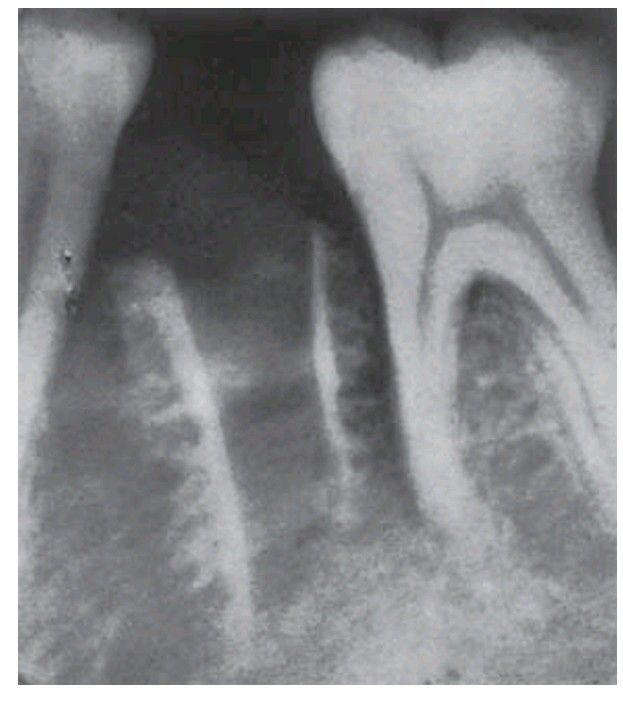

Sequestration in a severe dry socket.

Almost the whole of the lamina dura and attached trabeculae have become necrotic, forming a sequestrum. Healing is delayed while the sequestrum remains in place. Most dry socketrs are not associated with sequestration, or with only small sequestra.